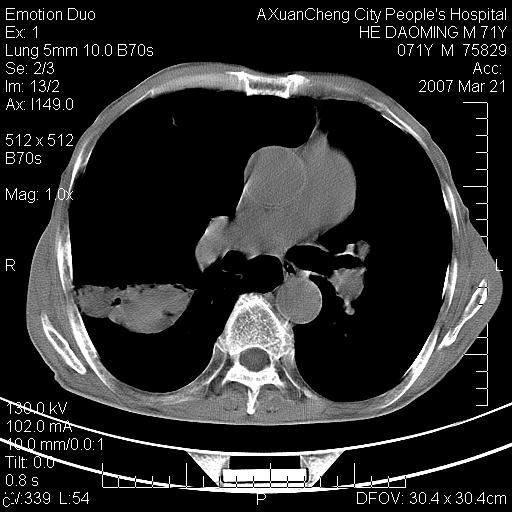

标题: CT7269:[原创] 咳嗽,咳痰,大家讨论右肺病变的部位 [打印本页]

标题: CT7269:[原创] 咳嗽,咳痰,大家讨论右肺病变的部位

右侧相当于叶间软组织样密度ct值约50hu,请大家讨论是什么性者病变

考虑:慢性支气管炎合并全小型肺气肿、肺大泡、间质纤维化、感染,右斜裂积液。

考虑:慢性支气管炎合并全小型肺气肿、肺大泡、间质纤维化、感染,右斜裂积液. 冠状动脉硬化(冠心病)

考虑慢支,肺气肿,肺大泡,间质纤维化;右侧斜裂液气胸考虑(可能因为肺大泡破裂破入斜裂所致).

考虑:慢性支气管炎合并右侧全小型肺气肿、肺大泡并感染、双肺间质纤维化,右斜裂积液。右侧斜裂液气胸考虑(可能因为肺大泡破裂破入斜裂所致).

如果患者变化一下体位扫描可分辨液平与斜裂的关系。